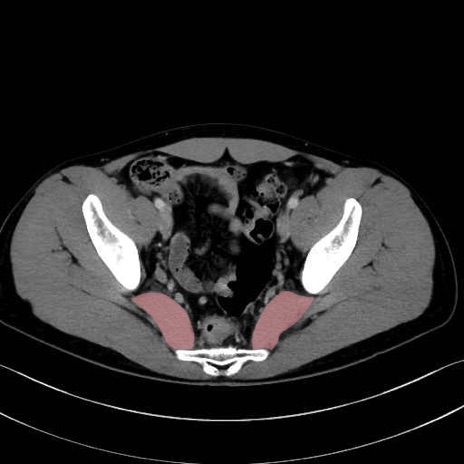

梨状筋 (Piriformis)